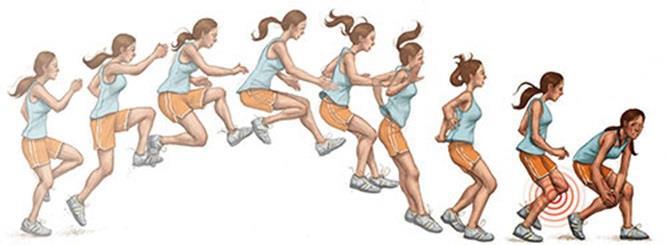

Oluş Mekanizması:

Sıklıkla ayak zeminde sabit duruken vucudun diz üzerinde dönmesi sonucunda ortaya çıkar.

Basketbol veya futbol gibi spor ile uğraşanlada koşarken yön değiştirmek için ani yavaşlama sonrasında ortaya çıkar. Özellikle çivili futbol ayakkabılarının zemine saplanması sonrasında ani dönme hareketi yapılırsa, ayak sabit iken gövde diz üzerinde dönmeye zorlandığında yırtık meydana gelebilir. Ayrıca sıçrama sonrasında diz üzerine kontrolsüz yüklenme de çapraz bağın yırtılmasına neden olabilir. Ön çapraz bağ yaralanması ile birlikte sıklıkla menisküs yırtığı da görülür.

Oluş Mekanizması:

Sıklıkla ayak zeminde sabit duruken vucudun diz üzerinde dönmesi sonucunda ortaya çıkar.

Basketbol veya futbol gibi spor ile uğraşanlada koşarken yön değiştirmek için ani yavaşlama sonrasında ortaya çıkar. Özellikle çivili futbol ayakkabılarının zemine saplanması sonrasında ani dönme hareketi yapılırsa, ayak sabit iken gövde diz üzerinde dönmeye zorlandığında yırtık meydana gelebilir. Ayrıca sıçrama sonrasında diz üzerine kontrolsüz yüklenme de çapraz bağın yırtılmasına neden olabilir. Ön çapraz bağ yaralanması ile birlikte sıklıkla menisküs yırtığı da görülür.